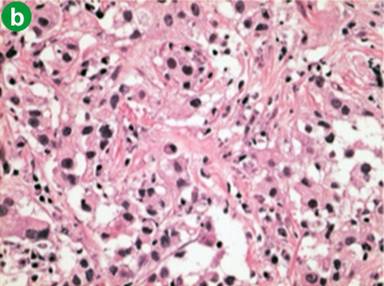

Following the diagnosis of autoimmune pancreatitis, screening CT images demonstrated pelvic lymph nodes that gradually increased in size (about 1.5 cm) and number. In June 2009, following CT detected an ill-enhanced hepatic tumor (Figure 3a). Endoscopic examinations denied upper and lower gastrointestinal tumors that could be the origin of hepatic tumor. Various candidates were considered, such as pseudotumor, cholangiocarcinoma, hepatocellular carcinoma, hepatic adenoma and metastasis of past bladder cancer. Percutaneous needle biopsy was performed to reach a final diagnosis. Histology of the biopsy tissue was urothelial carcinoma (Figure 3b), the same as in the bladder resected 5 years and 6 months previously (Figure 3c). The patient refused a second operation. Chemotherapy with gemcitabine was initially effective, but failed in one year, and metastasis developed in the adrenal gland, paranasal sinuses, and cervical vertebrae. Second line therapy by paclitaxel was not effective and the patient succumbed in January 2011.

Figure 3. Hepatic metastasis of the bladder cancer. a. CT showed an ill-enhanced, round-margined, tumor in the right lobe of the liver (arrow). b. Histology of percutaneous hepatic biopsy showed urothelial carcinoma, the same as that of urinary bladder resected 5 years and 6 months before (c.) (H&E, x100). |